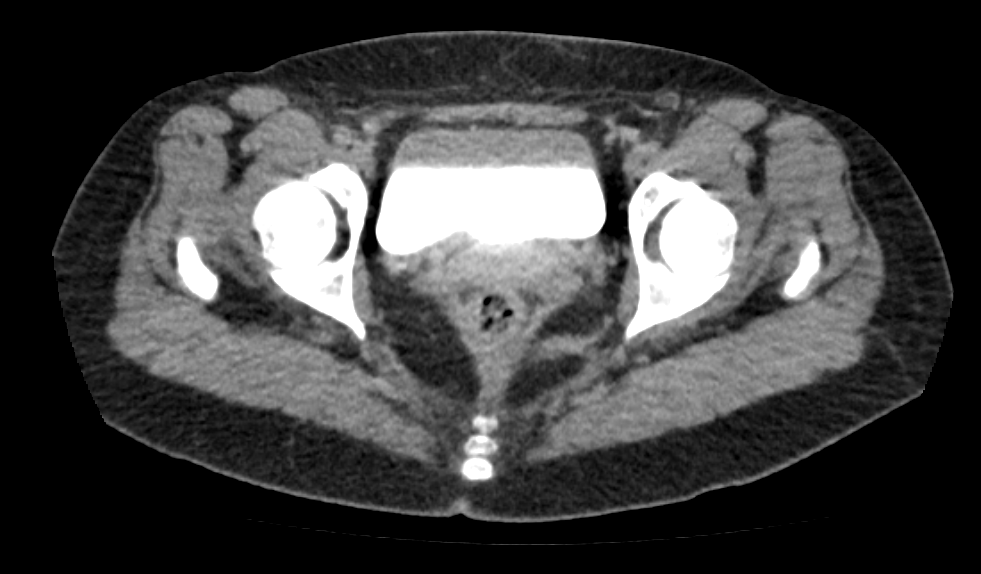

A tomografia da pelve ou pélvica é um exame de diagnóstico por imagem de alta qualidade, que permite analisar o abdômen inferior (fundo da barriga). O exame é indicado para detectar possíveis alterações da bexiga em ambos os sexos. A tomografia da pelve feminina possibilita analisar o útero e ovários (órgãos do aparelho ginecológico da mulher), já a tomografia pélvica masculina permite analisar a próstata e as vesículas seminais (órgãos do aparelho reprodutor dos homens). Contudo, o melhor método para analisar esses órgãos é a ressonância magnética.